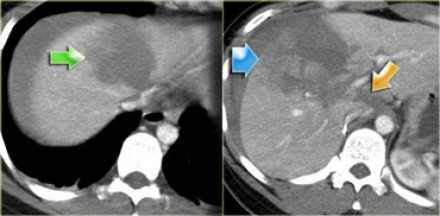

- Зеленой стрелкой указана гиподенсная зона, что соответствует гематоме.

- Желтой стрелкой указана гиподенсная линия, что соответствует разрыву.

- Синей стрелкой указана гиподенсная зона, соответствующая контузии.